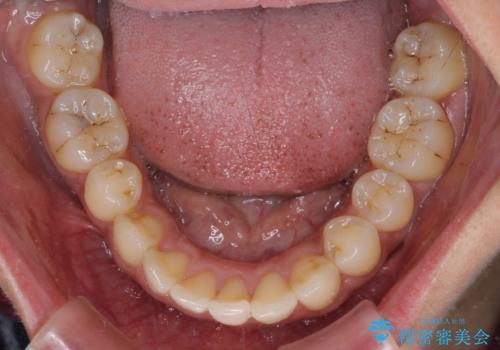

- 八重歯と上下前歯のでこぼこを気にして来院された患者様です。

上下前歯部叢生のスペース獲得のため、上下顎左右小臼歯各1歯(計4本)を抜歯して、ワイヤー装置にて矯正治療を行うこととしました。

上下の正中位置が大きくずれていたため、上下正中が合わないまま終了することが予想されましたが、思っていた以上にスムーズに歯が移動し、満足いただける仕上がりとなりました。